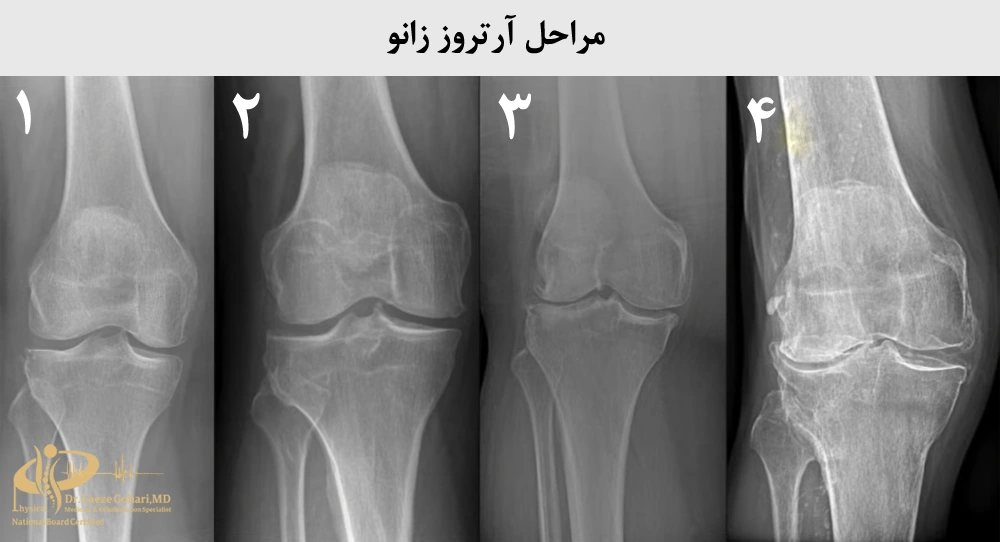

میزان تأثیر اوزون تراپی بستگی به مرحله آرتروز دارد. آرتروز زانو به چهار مرحله تقسیم میشود (منبع): بسیار خفیف (مرحله ۱)، خفیف (مرحله ۲)، متوسط (مرحله ۳) و شدید (مرحله ۴). اوزون تراپی برای بعضی مراحل آرتروز بسیار مفید است، اما در همه موارد اثرگذار نیست.

اوزون تراپی در مراحل 1 و 2: انتخابی اثرگذار برای بهبود درد و التهاب

اوزون تراپی برای مرحله ۱ و مرحله ۲ آرتروز زانو بیشترین اثربخشی را دارد (منبع).

در مرحله ۱ که غضروف تقریباً سالم است و علائم خفیف مانند درد یا سفتی جزئی در زانو پس از فعالیت زیاد بروز میکند، اوزون تراپی التهاب را کنترل کرده، درد را کاهش میدهد و حرکت زانو را بهبود میبخشد.

در مرحله ۲ که غضروف کمی ساییده شده و علائمی مانند درد یا خشکی هنگام راهرفتن، بالارفتن از پلهها یا فعالیتهای روزمره بیشتر میشود، اوزون تراپی همچنان التهاب و درد را کم میکند و از سرعت تخریب غضروف میکاهد.

اوزون تراپی در مراحل 3 و 4: اثرگذاری بسیار محدود

در مرحله ۳ و مرحله ۴ آرتروز زانو، اوزون تراپی تأثیر بسیار محدودی دارد و نمیتواند بهبود چشمگیری ایجاد کند.

در مرحله ۳ که غضروف به میزان قابلتوجهی ساییده شده و علائم شامل درد شدید هنگام حرکت، تورم مداوم و محدودیت در خمکردن یا صافکردن زانو است، اوزون تراپی میتواند تا حدی درد و التهاب را کاهش دهد، اما به دلیل شدت آسیب غضروف، اثر آن موقت است و نسبت به مراحل اولیه، بهبود قابلتوجهی در حرکت یا عملکرد مفصل فراهم نمیکند.

در مرحله ۴ که غضروف تقریباً کامل از بین رفته، استخوانها به هم ساییده میشوند و علائم شامل درد شدید حتی در حالت استراحت، سفتی کامل زانو و ناتوانی در انجام فعالیتهای روزمره است، اوزون تراپی تأثیر ناچیزی دارد و فقط در موارد نادر تسکین بسیار کوتاهمدت درد ارائه میدهد. حتی ممکن است با تأخیر در انتخاب روش مناسب، منجر به پیشرفت آرتروز شود.